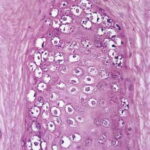

Verruca vulgaris = الثؤلول الشائع